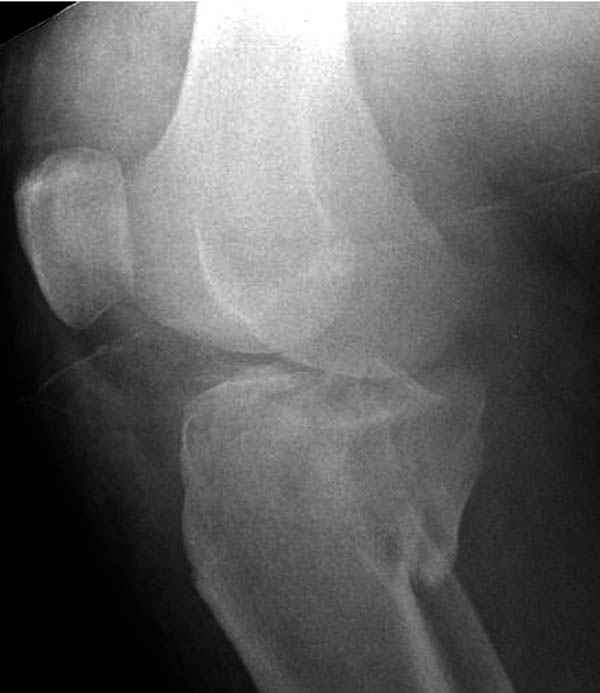

Трудно поверить, что разрекламированная Ортопедическая школа Восточной Украины позволяет такие странные снимки? На прямом снимке сохранен общий контур плато, но не известна судьба импрессии суставной поверхности. На полубоковой?, оставлен без репозиции задне-медиальный отдел, и навряд ли после такой фиксации можно удовлетвориться результатом.

Здесь как раз тот случай, когда результат зависит не только от мастерства хирурга, но и от наличия современных методов исследования. Например, КТ которая поможет рассчитать направления шурупов и установку импланта. Кроме этого, поможет определиться с доступом.

На представленных предоперационных срезах КТ огромный задне-медиальный фрагмент расположен больше кзади, чем медиально. Для планирования, кроме поперечных срезов, надо ориентироваться на корональные срезы, которые укажут топографию верхушки медиального фрагмента.

Представленные снимки не информативны, нужны отдельные качественные снимки коленного сустава и голени без ротации.